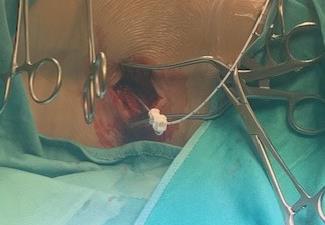

0 Unsustained or single discharge to train of stimuli

1+ Sustained discharge of appropriate muscle group. Ipsilateral response

2+ Sustained discharges of adjacent muscle groups, Ipsilateral

3+ Sustained discharges of distant muscle groups, Ipsilateral

4+ Sustained discharges of contralateral muscle group(s), with or without ipsilateral muscle group involvment